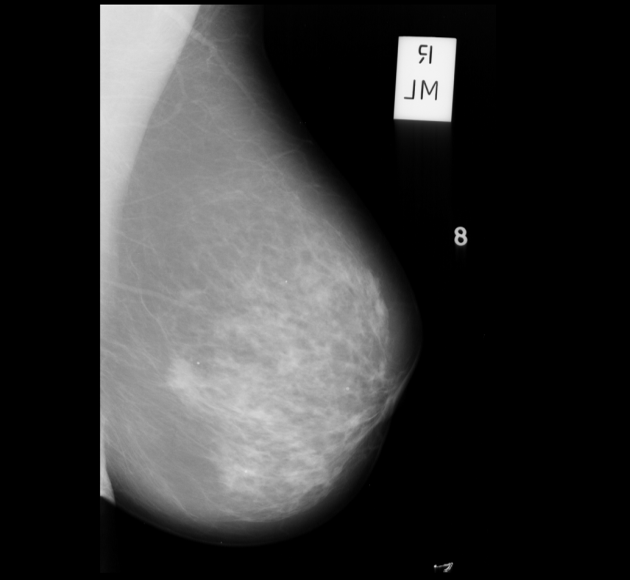

Neural networks require a large number of images as input for the training purposes. Because of limited resources of large dataset availability, the dataset used for this research is mini MIAS dataset [10]. It comprises of total 322 images which are further divided into a number of classes. Original size of each image in the dataset is 10241024. Sample images are shown in Figure 1.

Figure 5 shows a few sample images obtained after segmentation.